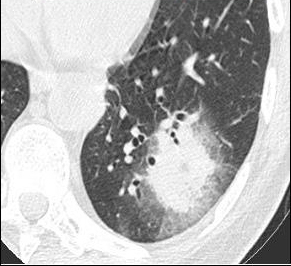

La fièvre persiste malgré les antibiotiques. Cela fait maintenant 5 jours, et vous décidez donc de réaliser un scanner thoracique dont les images sont les suivantes.

Question 13 : Comment décrivez-vous ces images ?

Nodule pulmonaire entouré de verre dépoli

Présence d’un épanchement pleural gauche

°précoce : signe du halo : nodule unique ou multiple, avec verre dépoli autour (signe du grelot se voit dans l’aspergillome compliquant une caverne tuberculeuse par exemple) ;